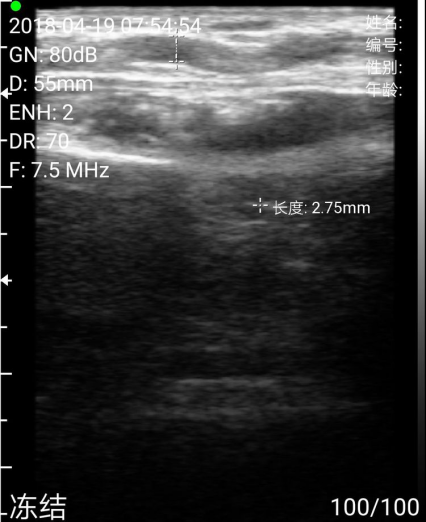

测量尺动脉直径(这里尺动脉有一个迂曲,术中有一点儿麻烦)